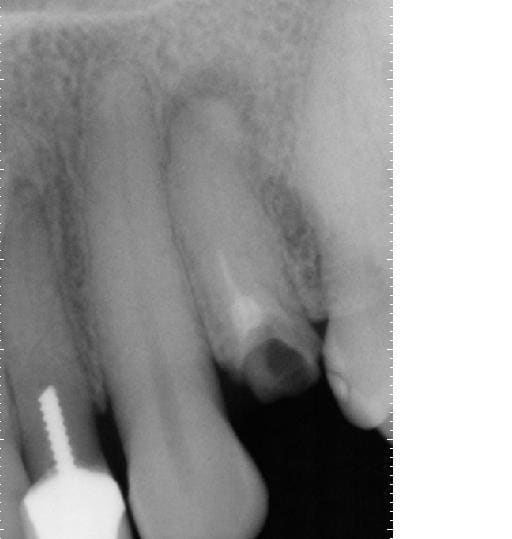

celle la faudra me dire comment on passe sans laser (et comment on y injecte autre chose que de la pate).

sinon: micjhel costeseque obture cortisomol lentulo+laser et ensuite maitre cone gutta (je l'ai vu y'a 15 jours).

le risque pate seule est qu'elle est trés trés compacte et dure.... pas gai pour une reprise de traitement et donc pate seule pour les 2 derniers mm mais cone foulé à chaud ensuite (je sais je faisais pas comme ça "avant" mais j'ai écouté les copains d'eugenol et me suis remis à la gutta.... par contre la digue....).

photo lime en place: pas possible aller + loin même en manuel avec une n°8....

1ere endo: lentulo pate trés fluide

2eme: premier tir et relentulo (pate trés fluide poussée par le laser et + épaisse pour la deuxiéme couche au lentulo)

3eme: deuxieme tir (je voulais chopper les 2 racines....) et relentulo et gutta.

ps: cette dent était donnée pour perdue et la seule proposition faite à la patiente était implant.... (idem pour la 22 qui est certes à refaire/reprendre mais sans doute pas perdue....)

y m'a fallu 30 minutes pour desobturer et réobturer, Sc33 sur tenoçns titane et coiffe provisoire posées cet aprtés midi, endo faite y'a 2 jours et RAS.